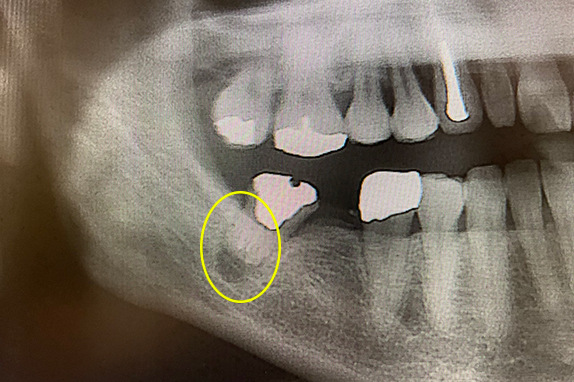

CASE 01 マイクロエンド(精密根管治療)+インプラント治療

-

- 主訴

- 痛くて噛めない(50代女性)

-

- 回数期間

- 6回 約3ヶ月

-

- 治療法

- マイクロエンド(精密根管治療)+インプラント

-

- 治療費用

- 約65万円(税抜)

右の奥歯が痛くて噛めないという主訴で来院。7番をマイクロエンドで完全し6番にインプラントを埋入したケースです。

<リスク・副作用>

術後は顔面の腫脹に加え、青あざができる場合があります。過度な衝撃や咬合を加えると補綴物の破折、脱落の可能性があります。